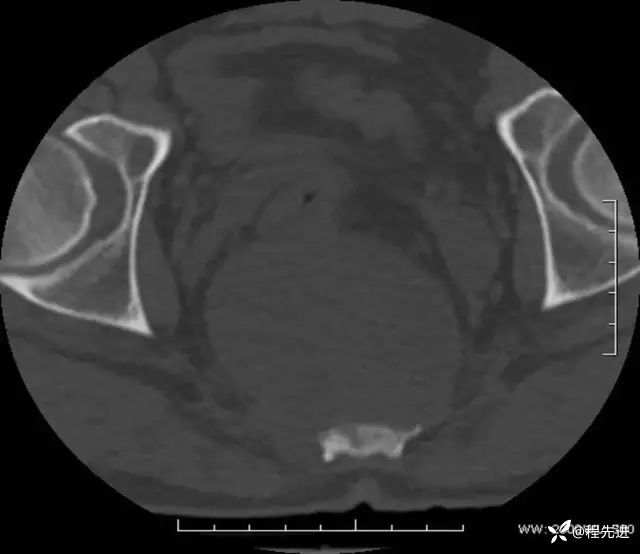

CT平扫:

骨窗: